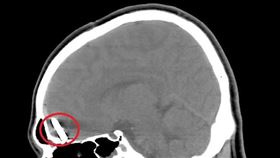

尪不倫怕被報復 打5寸釘進正宮頭顱

外遇者通常理虧在先,不敢對元配做出過分舉動,沒想到日...

長釘插入腦袋中 男頭痛兩天才就醫…

腦袋上插進一根釘子,竟然完全沒感覺?一名網友在社群網...

工人頭昏滴血 上醫院驚見釘子插很深

高雄一名25歲年輕裝潢工人,日前工作時,突然感到頭昏...